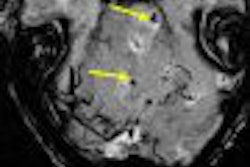

| Torn LTL. Above, transverse sonogram shows the dorsal aspects of the triquetrum (T) and lunate (L). The LTL fibers are not seen (arrow), which is consistent with a tear. Below, the LTL is not visualized on sonoarthrography (arrow) in the same patient. Note hypoechoic fluid extending between the triquetrum and lunate through the LTL tear. Intra-articular contrast improved visualization of the LTL tear. |